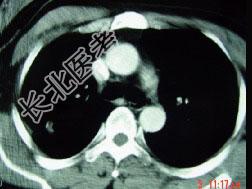

- 单项选择题男,32岁, 外出旅游1个月后,咳嗽1周, CT检查如图,最可能的诊断为 ( )